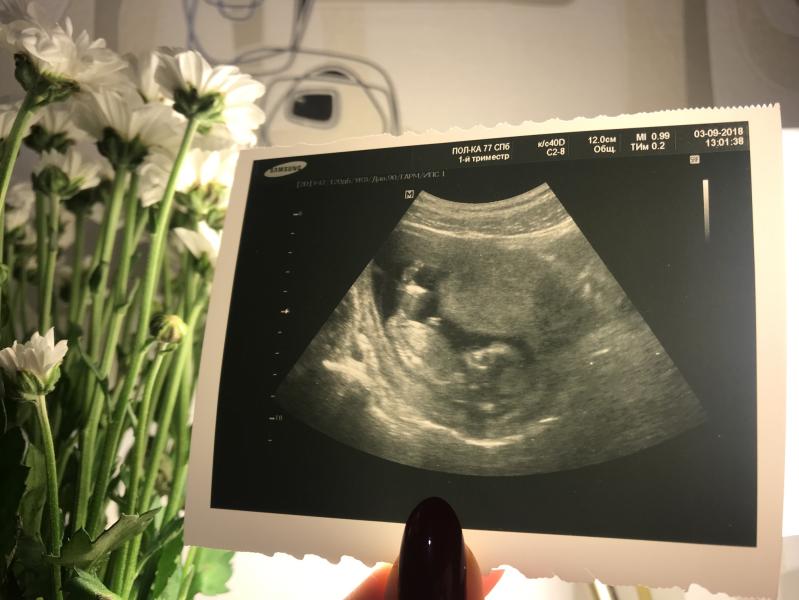

Первая фотография малыша😍

На каком сроке точно можно определить пол ребёночка?) когда идти?)